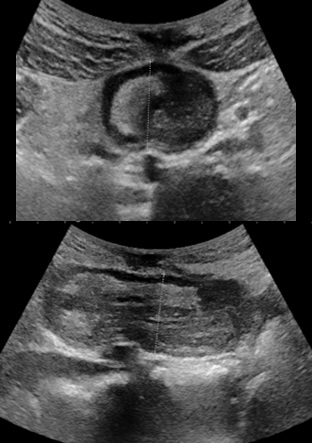

An hour later in the emergency room there is no more pain, a new ultrasound is requested which does not found the intussusception. He discharges and an appointment was set for him in three months in the event of no recurrence. The patient was seen again on the scheduled date and there was no recurrence or sign of complication. Seventeen months later from the first episode of invagination, the patient consults to the emergency room for episodes of severe abdominal pain localized in the epigastric region, of high intensity, without signs of irradiation and similar to those of the previous attack, no transit since two days (usual, consistent with his chronic constipation). The general condition of the patient is preserved, temperature at 36.4°C, pulse: 90 per minute, SaO2 : 100%, weight: 57.7 kg, digital pain assessment: 8, spontaneous ventilation ambient air: 18 cycles per minute, pale coloring, nauseous, but no vomiting. Physical examination revealed epigastric pain, a numb, helpless, unbloated abdomen, no palpable organomegaly. Ultrasound performed in an emergency found ileum intussusception at the epigastric location with the presence of a probable fatty structure mimiking to a mesenteric fat or a lipoma, a few visible common mesenteric lymph nodes, no coeliomesenteric or retroperitoneal adenopathy, there is no intra-abdominal fluid effusion (Figure 2).

Figure 2: Epigastric ileo-ileum intussusception with a transverse diameter of 4 x 3 cm. Presence of fatty tissue with vessels in the intussusception. (Mesenteric fat? lipoma?).